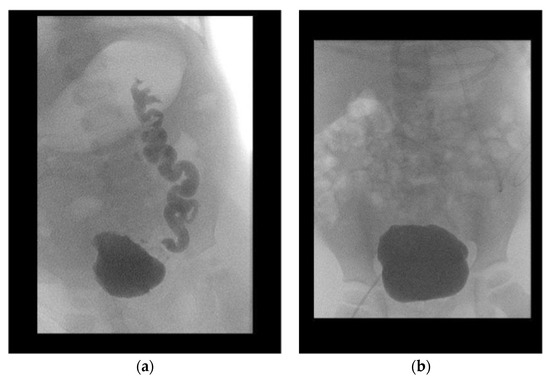

Because all patients had a valve unilateral reflux and dysplasia (VURD) syndrome, the initial treatment consisted of laparoscopic nephrectomy of the non-functioning kidney, and the entire ureter was used for UCP. Removal of the kidney was carried out using the extraperitoneal approach. The incision of choice for UCP is the Pfannenstiel method, except for patients who are expected to undergo a kidney transplant after UCP. In such patients, incision was carried out using the unilateral pararectal hockey-stick method to avoid a second scar. The dilated ureter (>10 mm) was dissected from the surrounding tissues with care to preserve its blood supply. The ureter was then incised at the anterior side and sutured together in a U-shape forming a sheet (Figure 1). The bladder was then incised starting from the vesicoureteral junction towards the posterior wall, and the ureter sheet was sutured to the bladder wall.

Figure 1. Anteriorly incised megaureter (a); U-shaped megaureter (b).